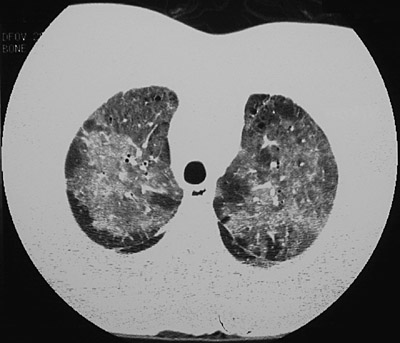

| This CT scan of the chest with the "lung window" setting reveals extensive irregular opacifications in all lung fields as a consequence of pulmonary alveolar proteinosis. The view in the upper lobes seen below demonstrates that the process is decreased toward the periphery. |